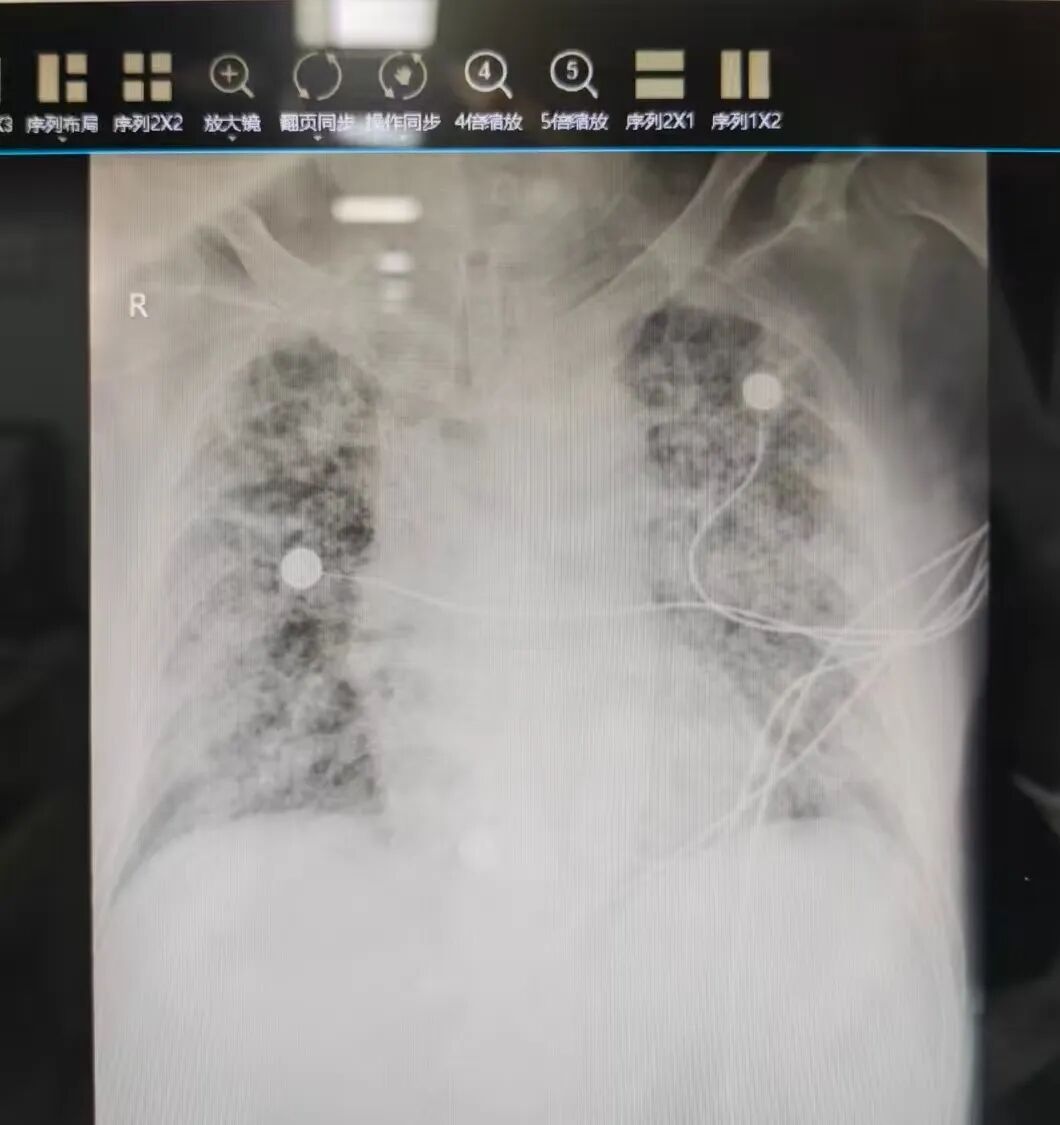

重症肺炎引发的急性呼吸窘迫综合征(ARDS),常导致患者肺部气体交换功能几近停滞,出现顽固性低氧血症,即便使用有创呼吸机给予高强度的通气支持也难以奏效,死亡率极高。ECMO技术的本质,是在此危急关头,暂时代替患者的心肺功能,将患者血液引出在体外进行氧合后再回输体内,为已不堪重负的肺脏赢得宝贵的“休息”与“修复”时间,为治疗原发病争取至关重要的时间窗。 精准决策,迅捷响应: 以专业体系筑牢安全基石

ECMO治疗的成功,始于精准的决策,并非所有危重患者都适合,时机把握至关重要。面对每一例潜在适应症患者,王胜主任亲自指导与严格把关,带领科室团队启动多维度评估,在最短时间内完成病情研判,确保每一次上机决策都科学、审慎、及时,真正做到“该上则上,精准施治”,从源头上保障了治疗的安全性与有效性。启动ECMO治疗程序后,训练有素的ECMO医护团队即刻无缝衔接。医生团队在超声引导下进行经皮血管穿刺置管技术(VA/VV-ECMO),操作精准高效,为ECMO系统的顺利运转建立可靠的生命通路。ECMO管理是对护理团队专业能力的极致考验,目前重症医学科已形成系统化的ECMO专职护理方案,涵盖管路安全、感染防控、抗凝管理、血流动力学监测、肢体血运观察、并发症预警及早期康复等全方位照护。护士们24小时严密守护,时刻警惕着任何细微的病情变化,确保这台“生命引擎”平稳运行,为患者提供最安心的支持。ECMO不仅仅是一台机器,更是一套集顶尖医疗技术、丰富临床经验和高度团队协作于一体的生命支持体系。